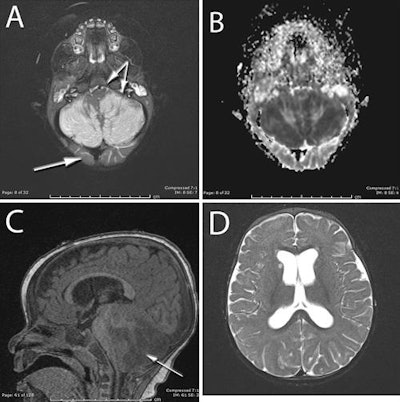

MR images revealed severe swelling in the child's cerebellar hemispheres but no damage to the upper part of her brain soon after she was found unresponsive and barely breathing. That's the reverse of what usually happens in cases of oxygen deprivation, leading quick-thinking pediatric emergency physicians and neurosurgeons to look for another cause.

An MRI scan then showed severe swelling in the cerebellar hemispheres, which blocked the normal flow of cerebrospinal fluid. The MR images showed no damage to the upper part of the baby's brain.

The researchers noted that the MRI results were unusual because in most cases, the upper part of a person's brain is damaged from a lack of oxygen and the cerebellum is spared. This reversal of common findings suggested a specific association with ketamine.

Six months after the incident and despite MR images showing permanent damage to the cerebellum, the child has achieved anticipated developmental milestones and normal muscle coordination, but with a slight delay in speech progression.